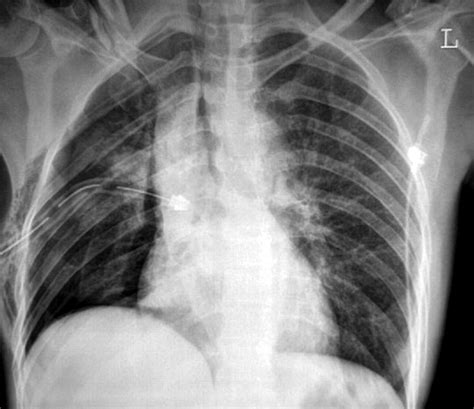

Pneumothorax Chest Tube : CXR showing right sided chest tube and resolution of pneumothorax. | Download Scientific Diagram / Collapsed lung (pneumothorax)—this occurs when air has built up in the area around the lungs (the pleural space) from a leak in the lung.

SGEM#300: The Lung is Up Where it Belongs - With or Without a Chest Tube | The Skeptics Guide to ...

SGEM#300: The Lung is Up Where it Belongs - With or Without a Chest Tube | The Skeptics Guide to ... from www.thesgem.com